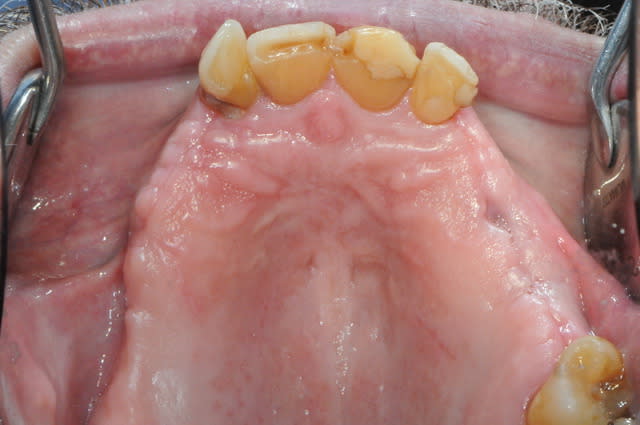

si ça peux alimenter ta réflexion...

manque d'intelligence de ma part j'ai pas fait de photo du cas au tout départ. mais la première photo devrait vous donner une idée du reste...

la suite c'est pose 4 implants, ceramique, stellite sur locators (beaucoup moins couteux qu'une barre et plus facile à nettoyer)